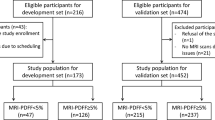

This prospective study involved multi-institutional cohorts in Japan. Online Resource 1 shows the study protocol. Patients were recruited from seven liver centers throughout Japan—namely, Ehime University Hospital, Ogaki Municipal Hospital, Suita Municipal Hospital, Kagoshima City Hospital, Kurume University Hospital, Sasebo City General Hospital, and National Hospital Organization Nagasaki Medical Center. A total of 846 patients with chronic liver disease who underwent MRI-PDFF and iATT from May 2021 to March 2023 were enrolled. However, patients (i) who were unable to hold their breath for several seconds for iATT measurement; (ii) who might experience difficulties in undergoing MRI owing to claustrophobia, presence of magnetic material within their bodies, tattoos, implanted pacemakers, etc.; or (iii) who did not consent to study participation were excluded from the analysis.

A total of 846 patients were enrolled in this study after excluding 13 patients (VsN < 50%, 2; interquartile range/median > 30%, 10) (Online Resource 1). Table 1 summarizes the characteristics and laboratory data of the enrolled patients. The median body mass index was 24.8 kg/m2 (IQR, 22.1–28.1 kg/m2). The median skin-to-capsula distance (SCD) was 18 mm (IQR, 15–20 mm).